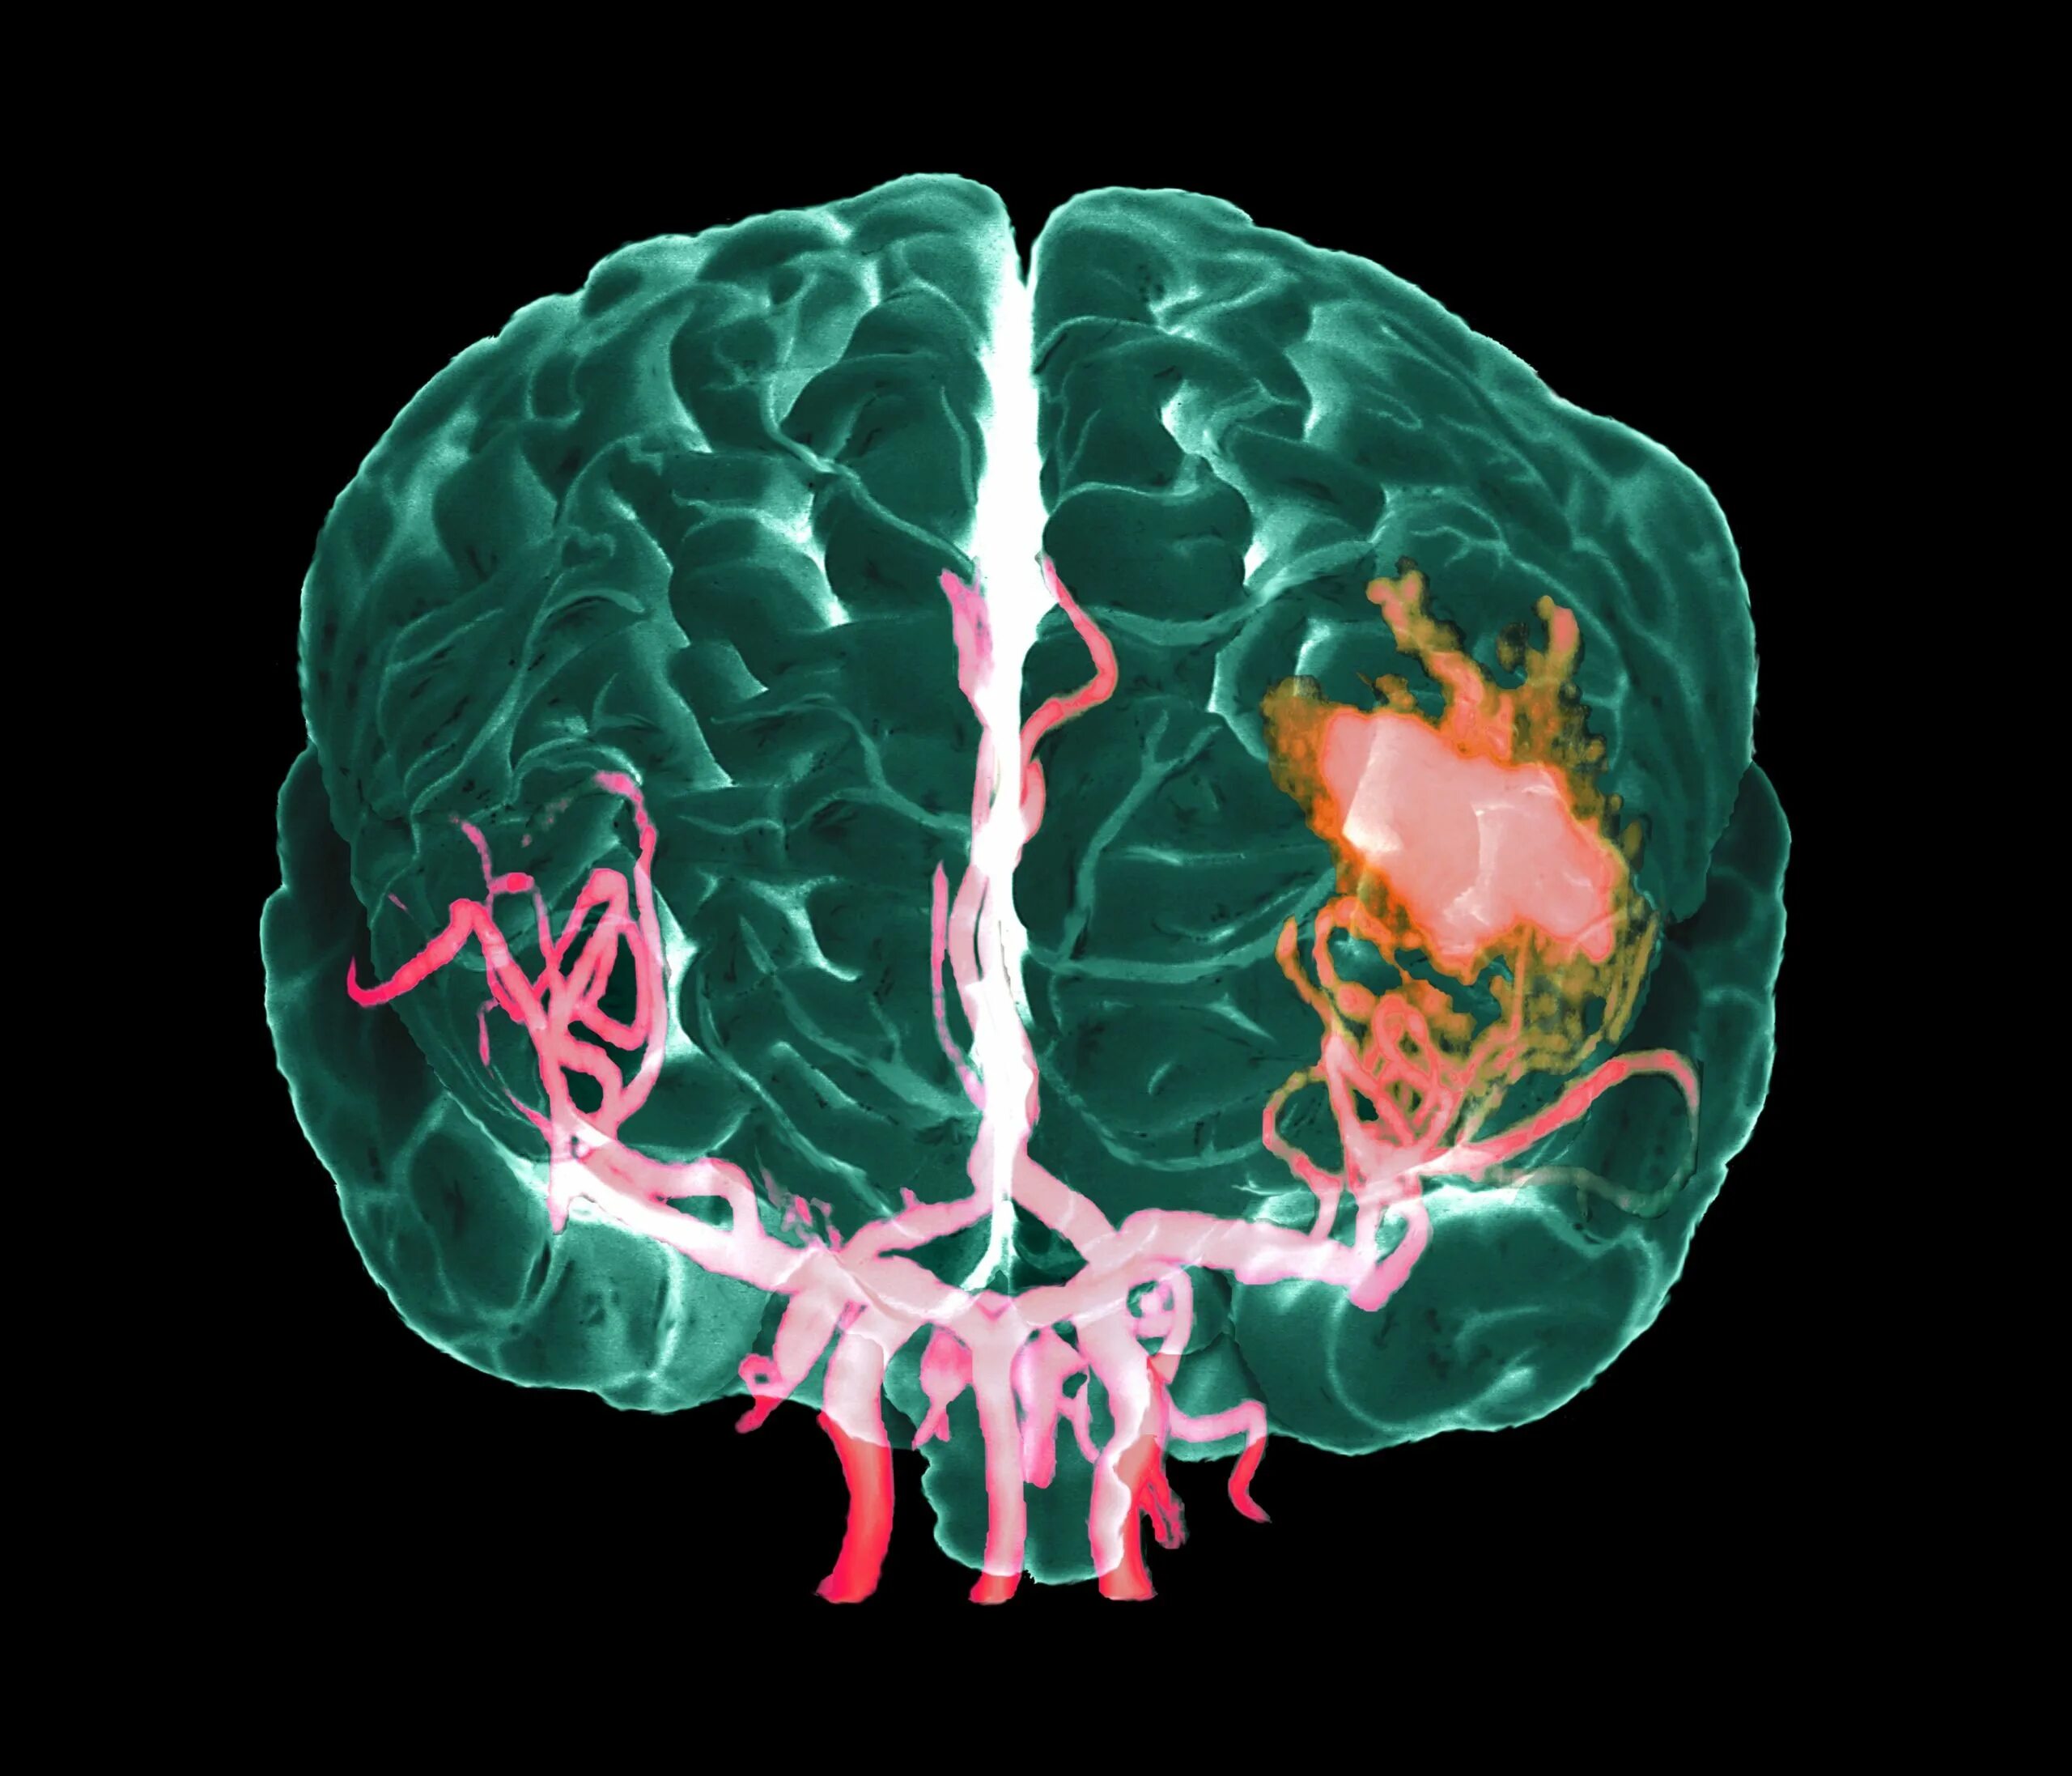

Лопнул сосуд в головном